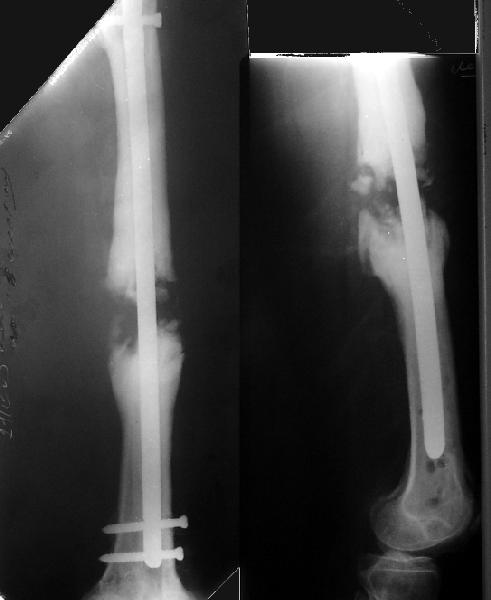

Рефрактур уж точно можно будет не опасаться, а за несколько месяцев даже при отсутствии заполнения костью по всей окружности, этот обходной "мостик" упрочнится и возьмет на себя нагрузку. В приложении пример такого рода "эндопротезирования диафиза", прошло больше 3 лет.

Пациентка, страдающая еще и инсулинозависимым диабетом, не хромает, работает инженером.